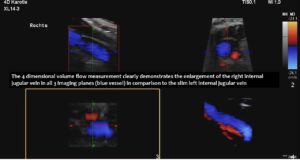

Consequently, blood had difficulty leaving the skull, resulting in continuously increased pressure and severe headaches, as well as other neurological dysfunction. The left side was more affected due to the double compression. This was clearly demonstrated by four-dimensional volume flow measurements in both jugular veins.

Only a four-dimensional volume flow measurement of the jugular veins can determine the cause of the daily headaches. The overall reduction in venous outflow from the brain in both jugular veins, totalling 258 mL/min, is significantly lower than the normal average volume of 719 mL/min. Consequently, the patient can eliminate only 36% of the required flow volume, while additional volume is forced into the skull from the left renal vein via the tronc réno-rachidien and from the left common iliac vein via the left ascending lumbar vein. This results in a chronic increase in intracranial pressure, as demonstrated by the elevated cerebrospinal fluid pressure obtained through a lumbar puncture. When the left jugular vein is also completely compressed due to increasing cervical lordosis when upright, the headaches become unbearable, accompanied by additional neurological symptoms as described by the patient.

Without this sophisticated technique, it would be unclear how severe the pressurization of the skull was and that, despite compression of both jugular veins, the right one was the main escape route from the skull.